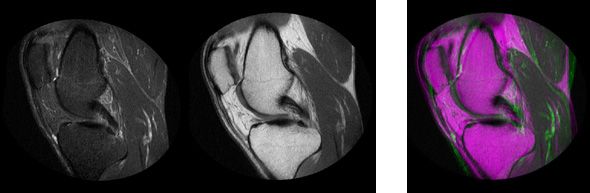

Image registration is an image processing technique used to align multiple scenes into a single integrated image. It helps overcome issues such as image rotation, scale, and skew that are common when overlaying images.

Image registration is often used in medical and satellite imagery to align images from different camera sources. Digital cameras use image registration to align and connect adjacent images into a single panoramic image.